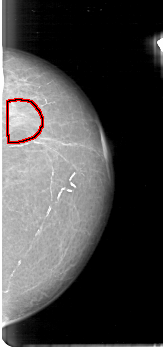

D_4072_1.RIGHT_MLO

FILE: D_4072_1.LEFT_MLO.OVERLAY

TOTAL_ABNORMALITIES 1

ABNORMALITY 1

LESION_TYPE MASS SHAPE IRREGULAR MARGINS OBSCURED

ASSESSMENT 0

SUBTLETY 2

PATHOLOGY BENIGN

TOTAL_OUTLINES 1

BOUNDARY